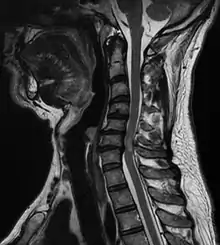

| A tumour causing spinal cord compression | |

Diagnosis is by X-rays but preferably magnetic resonance imaging (MRI) of the whole spine.[1] The most common causes of cord compression are tumors, but abscesses and granulomas (e.g. in tuberculosis) are equally capable of producing the syndrome. Tumors that commonly cause cord compression are lung cancer (non-small cell type), breast cancer, prostate cancer, renal cell carcinoma, thyroid cancer, lymphoma and multiple myeloma.